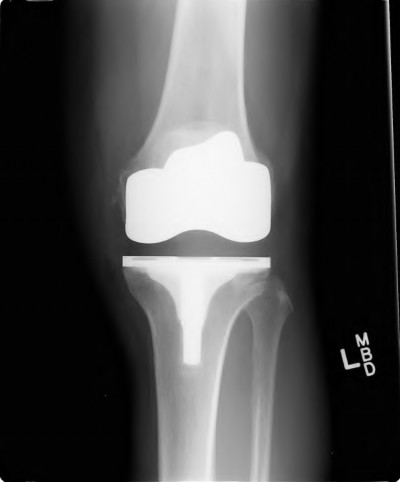

A 72-year-old female presents with progressive left thigh and knee pain for the last year. 5 years ago she sustained a femoral neck fracture treated with the implant seen in Figures A-C (current radiographs). The thigh pain is worse with weight-bearing. C-reactive

protein and erythrocyte sedimentation levels are within defined limits. Which of the following is the most likely cause of her pain?